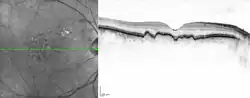

Bereits Donders beschrieb in seinem wissenschaftlichen Aufsatz das unterschiedliche Aussehen von Drusen. Klinisch wird heute zwischen harten und weichen Drusen unterschieden, in Abhängigkeit ihrer Ränder, sowie weiters von kalzifizierten Drusen, wenn diese funduskopisch einen hochreflektiven weißlichen Inhalt aufweisen.[4] Histologisch wurde jedoch eine wesentlich größere Vielfalt an unterschiedlichen Drusenformen beobachtet.[5] Eine ähnliche Vielfalt findet sich in den Tomographieschnitten der Optischen Kohärenztomographie.[6]